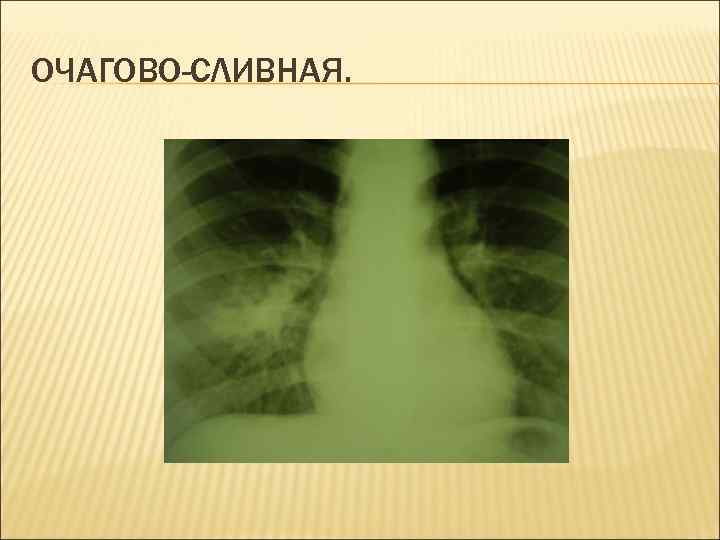

ОЧАГОВО-СЛИВНАЯ.